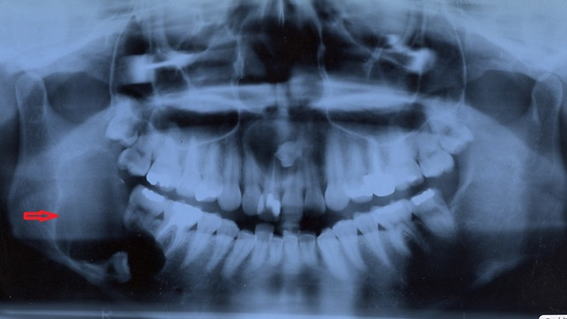

28歳女性 エナメル上皮腫